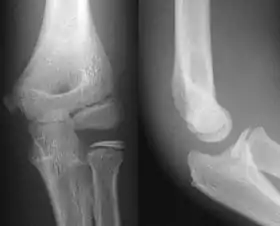

AP and lateral elbow X-ray

• Elbow - AP and Lateral. Radial head projections available on request